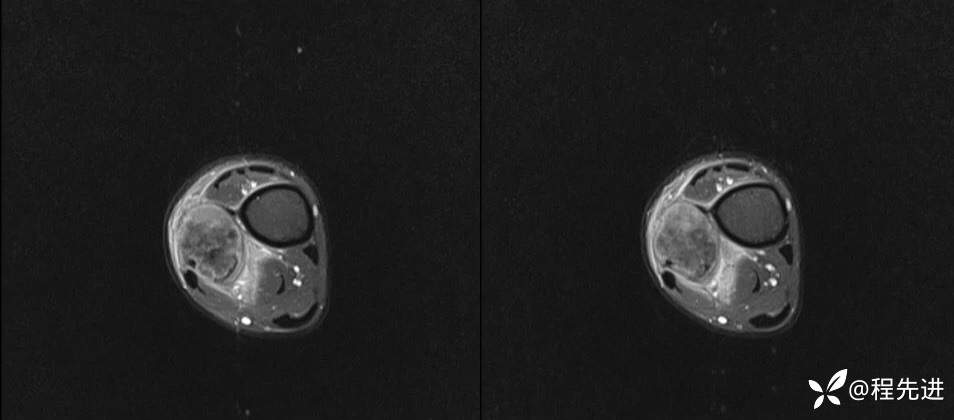

MR

T2

T1

T1+C